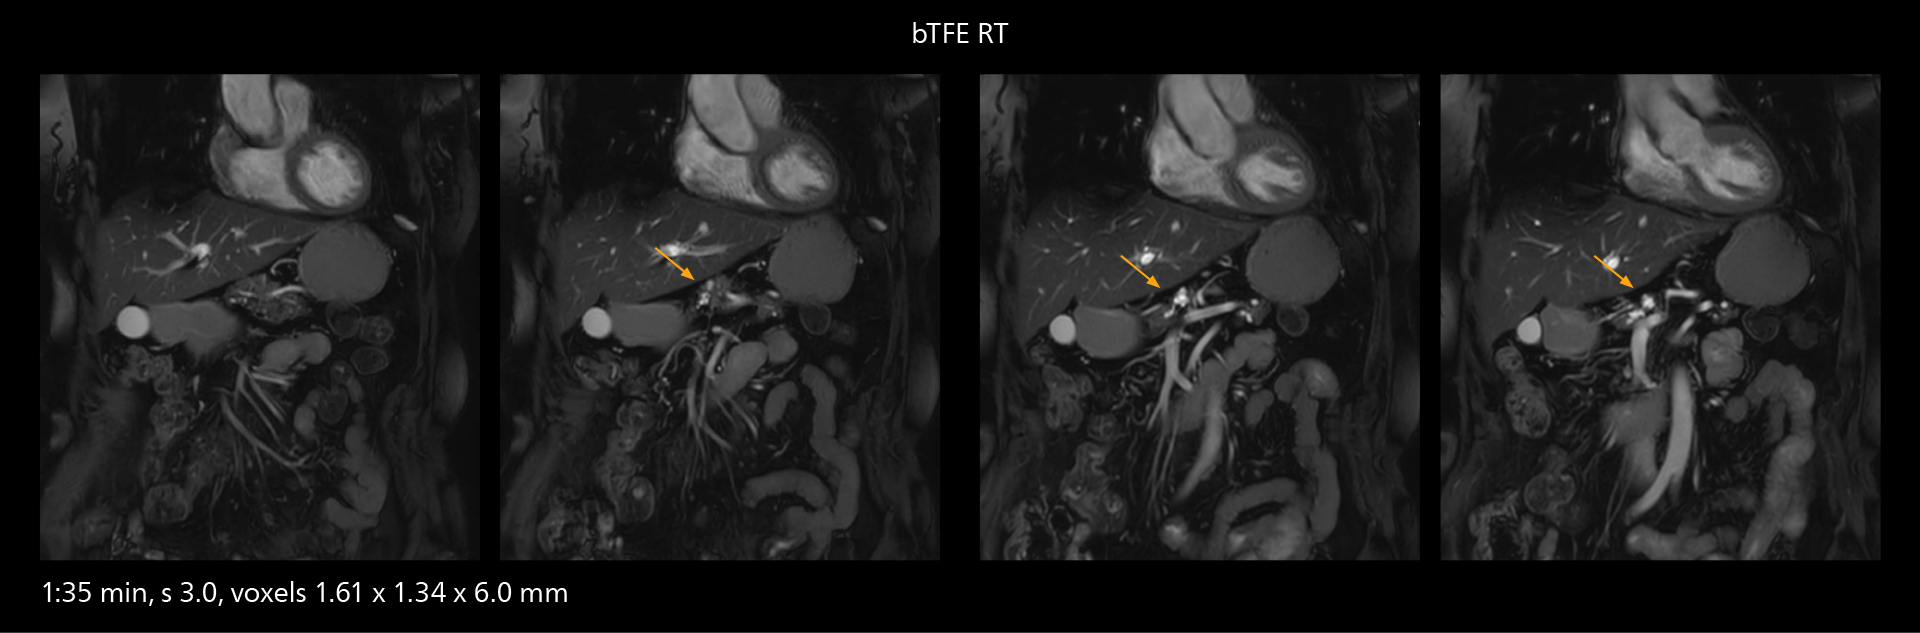

SmartPath to Elition X comes with Smart Workflow technologies that support technologists and can save them time. VitalEye for touchless patient sensing is one example. “The implementation of VitalEye respiratory synchronization has had a significant impact,” says MR technologist Yoshihiro Otsu, Chief of the Radiological Department. “It not only improves workflow, but it also has increased the quality of examinations. Particularly for the large number of MRCP examinations performed in this hospital, VitalEye has increased the possibility to obtain sharp images with less blurring. Clinicians here really appreciate this improvement in MRCP image quality.” The VitalScreen on the scanner has helped reduce the risk of patient misidentification. “It allows patient information to be viewed in the magnet room when standing next to the patient,” he says. “And the automated patient centering in the magnet is very useful as well.” Apart from reducing stress for technologists, Smart Workflow helps improve respiratory synchronization and reduce examination stress for the patient.

With SmartPath to Elition X, the MRCP examinations at Sannodai Hospital benefit from VitalEye: respiratory synchronization is possible without respiratory belt positioning and image quality is excellent.